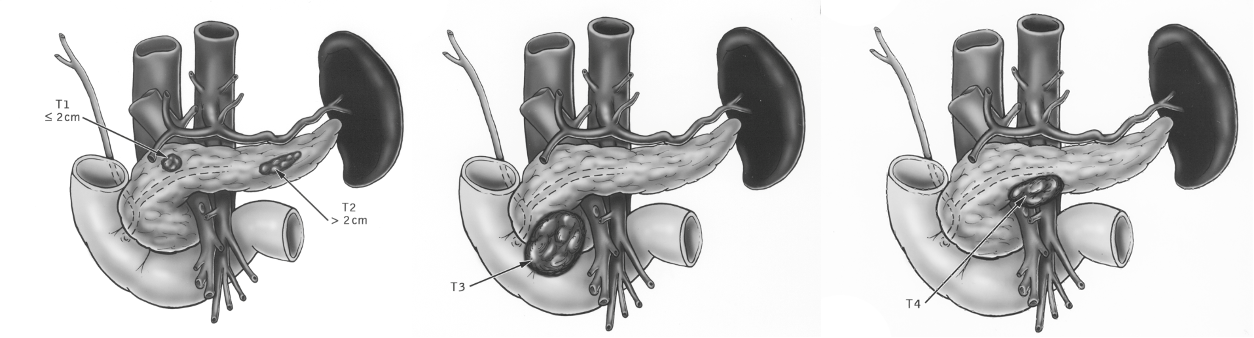

Tumor Staging according to the TNM System

T1 = <2cm

T2 = 2-5 cm

T3 = >5 cm

T4 = Invasion of adjacent tissue